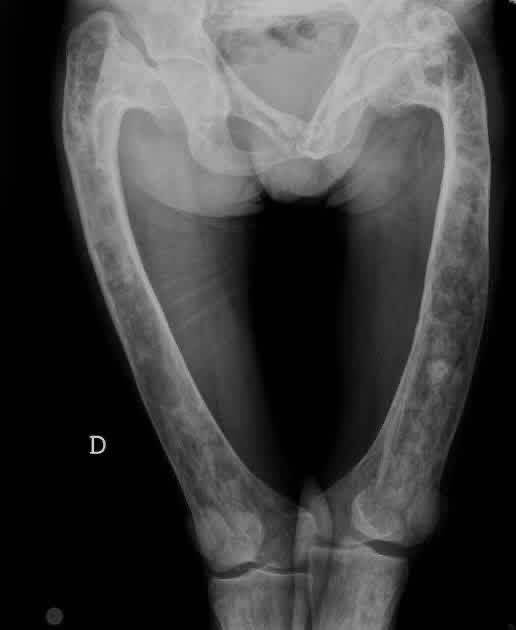

30 years male with bilateral hip pain with a long history of steroid intake. How do i manage? #Orthopedics #xray #health @dr_manish_ydv @Dr_Shiv_kumar_ @DrAkhilX @IhabFathiSulima @DrMedica_13 @drobiy12 @hemo_shk

albertoortegana's tweet image. 30 years male with bilateral hip pain with a long history of steroid intake. How do i manage?

#Orthopedics #xray

#health

@dr_manish_ydv @Dr_Shiv_kumar_ @DrAkhilX @IhabFathiSulima @DrMedica_13 @drobiy12 @hemo_shk